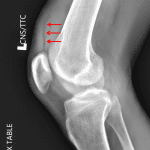

- Large lipohemarthrosis

- No acute fracture identified

- Lipohemarthrosis

Large lipohemarthrosis without acute fracture identified. Consider CT for further evaluation.

- Cross-table lateral knee views are important in the setting of trauma to evaluate for lipohemarthrosis

- Lipohemarthrosis often results from an intra-articular fracture resulting in release of fat (“lipo”) and blood (“hemo”) into the joint space

- Look for a layering fat-fluid level on cross table lateral view

- When you see lipohemarthrosis and don’t see a fracture, always raise the possibility of an occult fracture and suggest CT or MRI for further evaluation

- This patient had an impaction fracture of the medial femoral condyle that was even subtle on CT